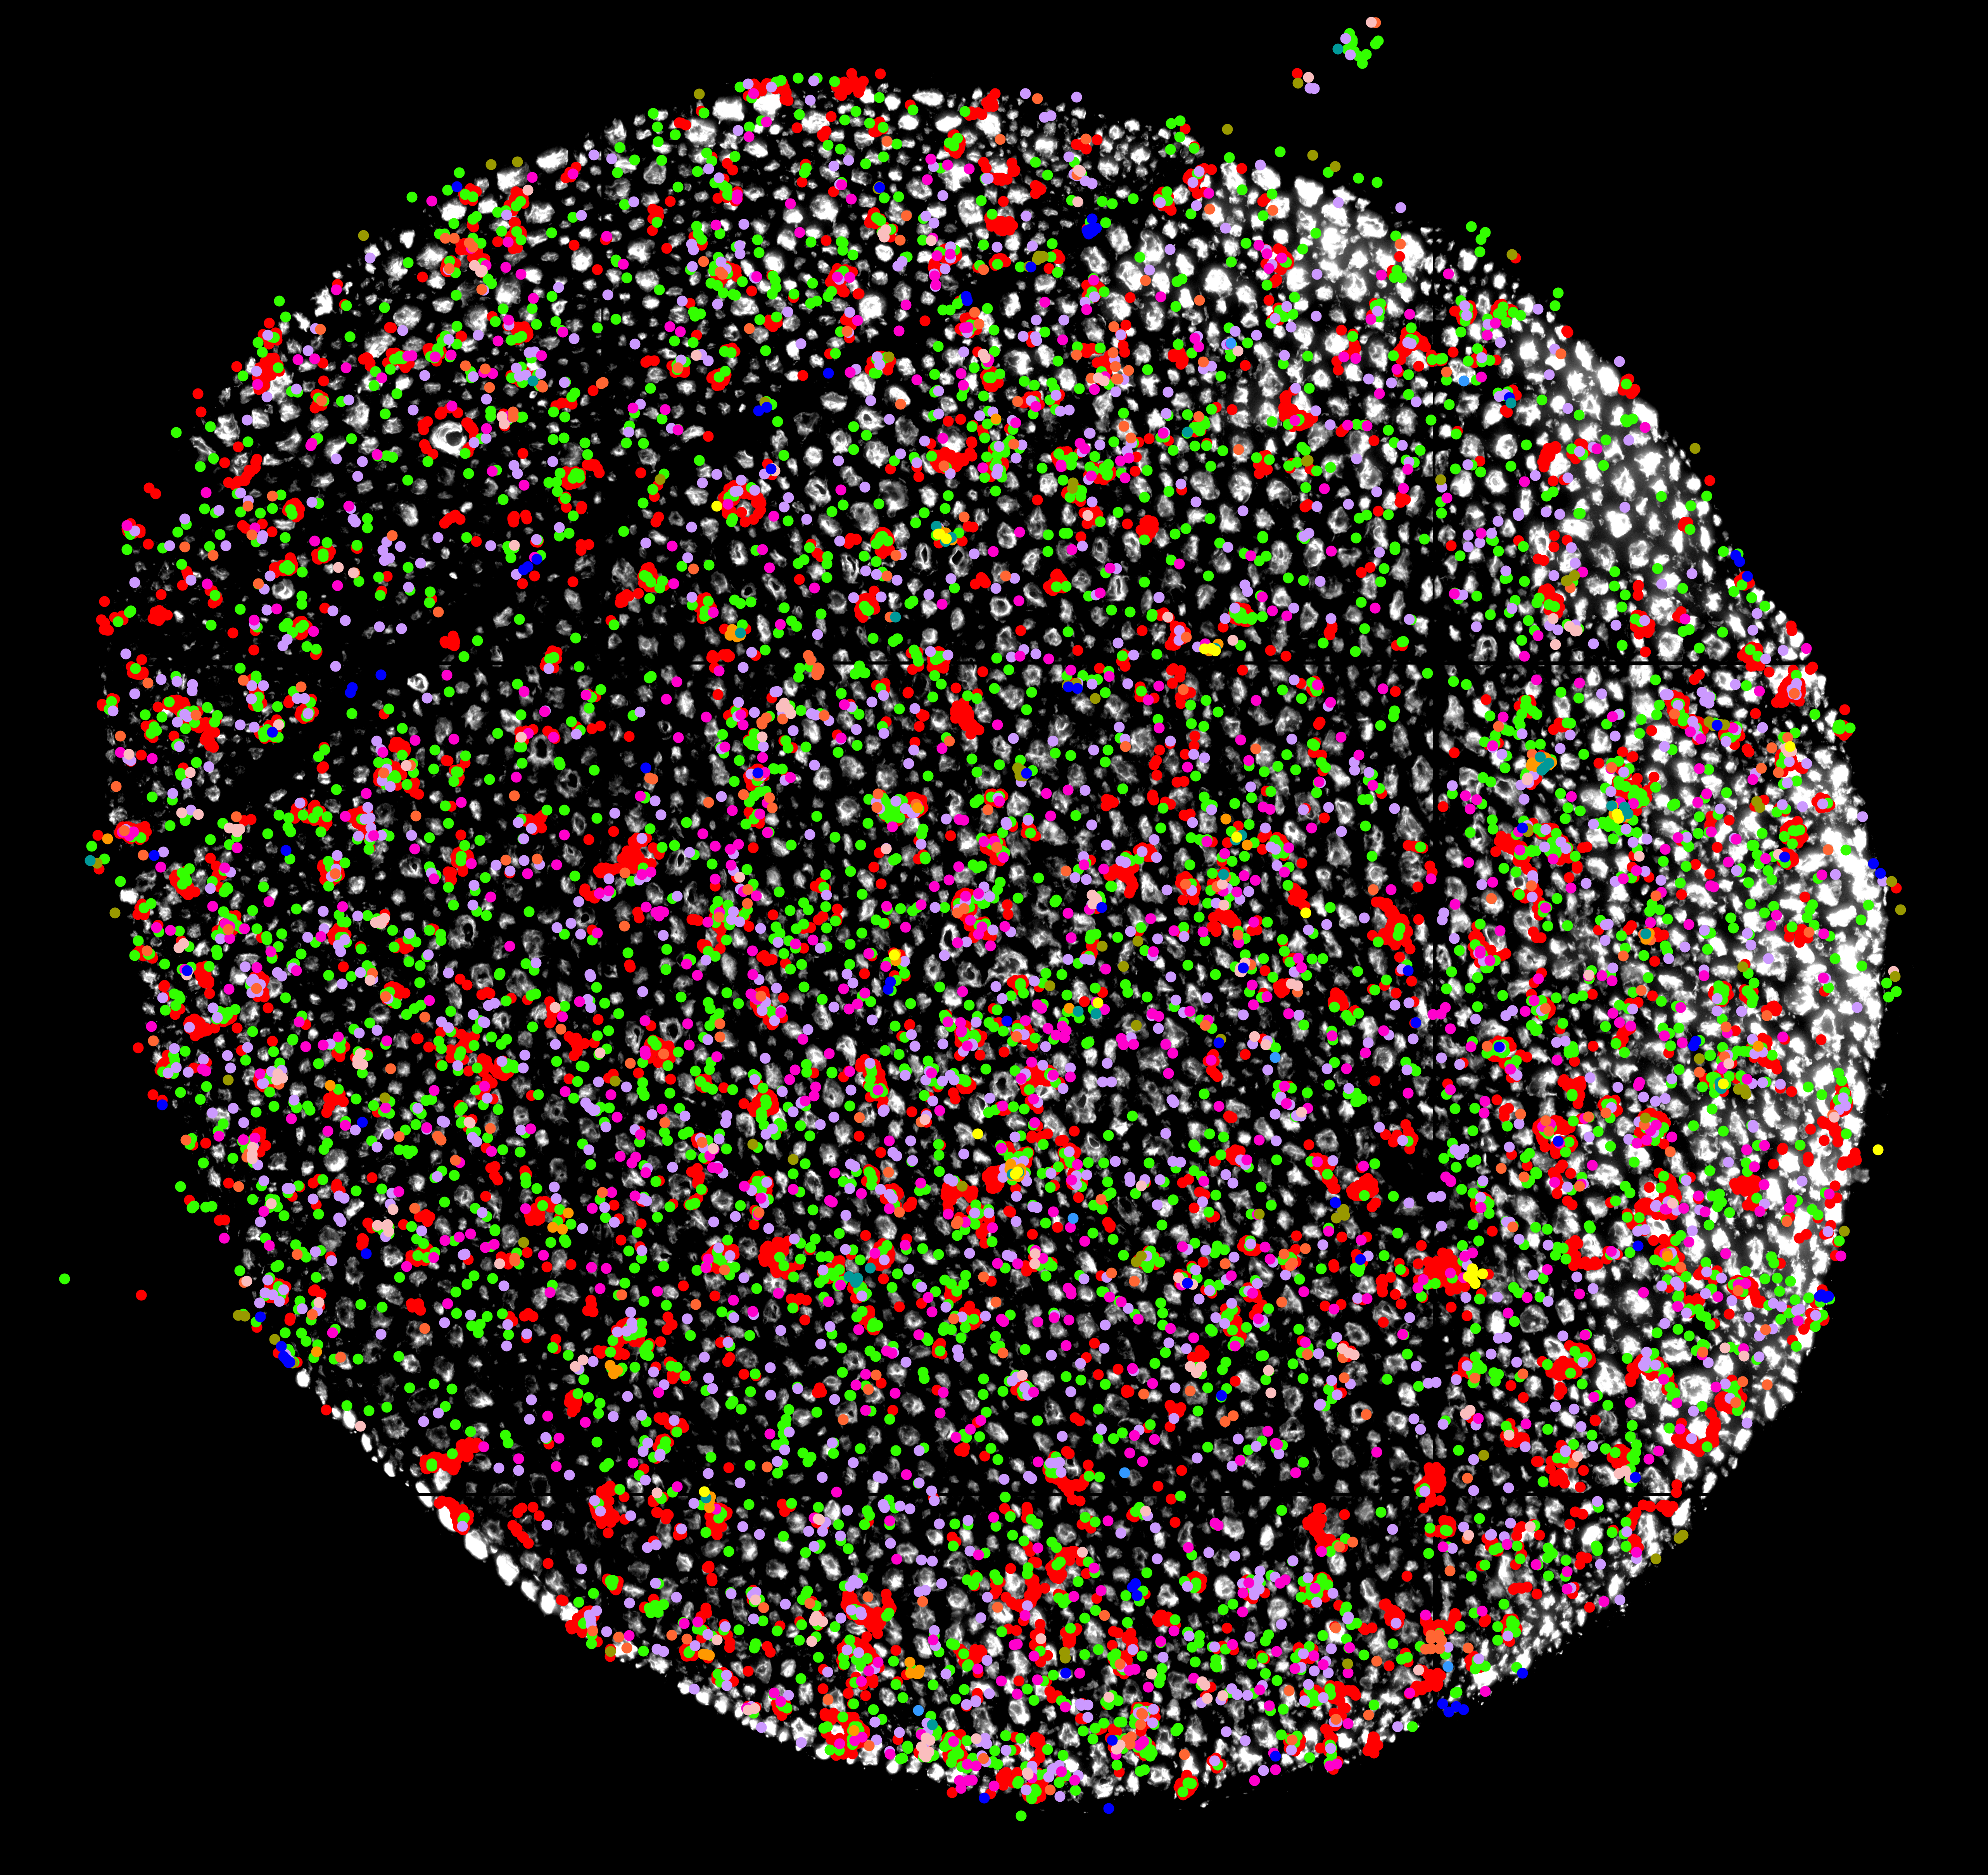

Motor neurons depend on local protein production within their axons to support their long-distance connections to muscles. Using advanced spatial transcriptomics, scientists at the VIB–KU Leuven Center for Brain & Disease Research analyzed gene expression separately in neuron cell bodies and axons in adult mice. They found that axons contain unexpectedly high levels of the molecular machinery needed to make proteins.